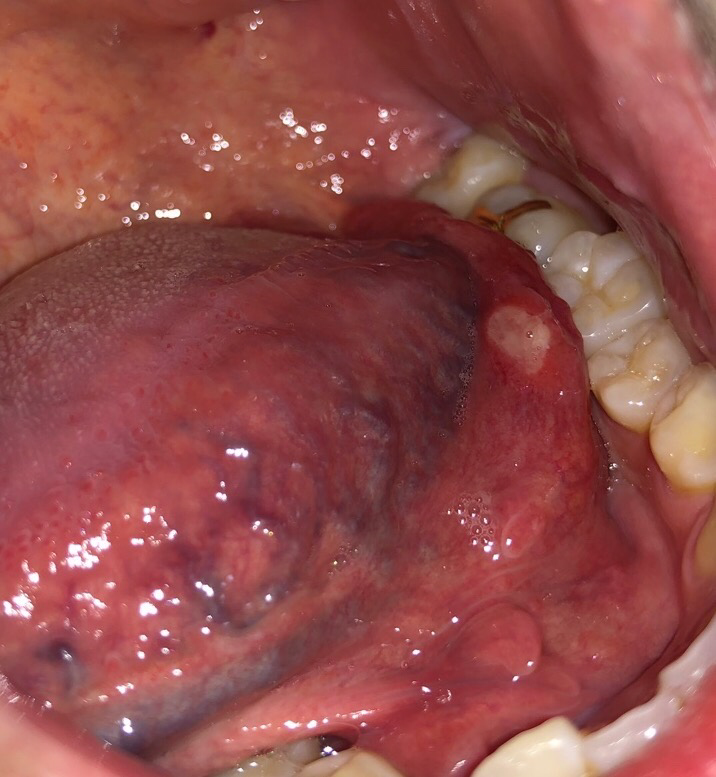

구강암은 아니니 걱정하지 않으셔도 됩니다. 구내염이며 구내염은 시간이 오래 지나야 괜찮아 지실꺼에요 .

시간이 경과하면 호전되는 경우가 많은 구내염 같습니다..정기적인 스케일링과 구강 양치액을 사용해 구강청결을 유지해 줍니다..입안을 깨끗하게 유지하고 수분 섭취를 자주 합니다..짜고 맵고 신 자극이 강한 음식은 피합니다.